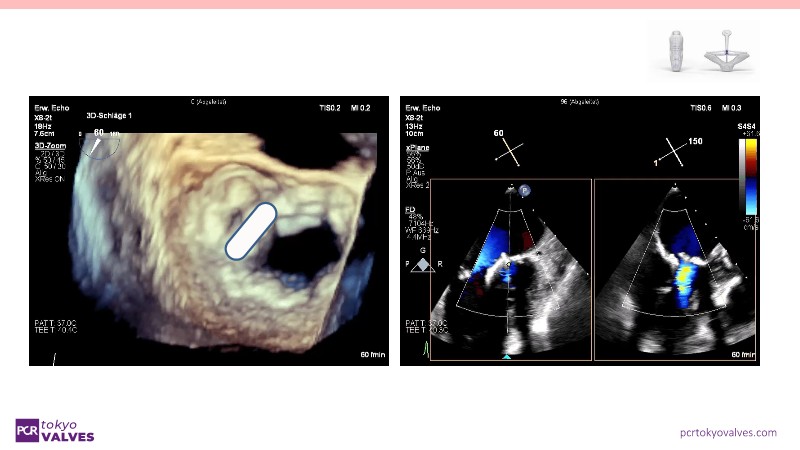

Through case reviews, explore the latest advancements in transcatheter edge-to-edge repair (TEER) for degenerative mitral regurgitation. Discover how a novel TEER device expands treatment possibilities, offering predictable and durable results.